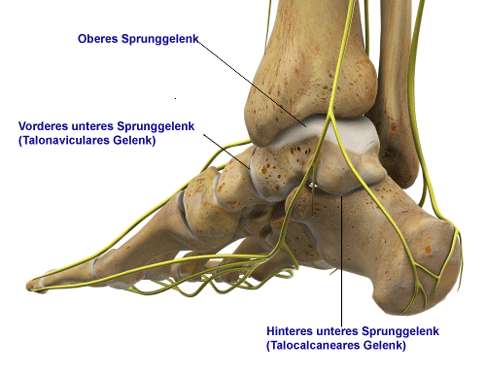

Schließt vorne gelenkig an das Sprungbein an. - Unteres Sprunggelenk:

Wird aus Fersenbein, Sprungbein, Kahnbein und Würfelbein gebildet. - Arthrodese (Versteifung):

Die Triple-Arthrodese führt zu einer deutlichen Einschränkung der Funktion des unteren Sprunggelenks. Das ist vor allem auf unebenem Boden spürbar: Die Neigung im unteren Sprunggelenk ermöglicht das Gehen am Hang oder auf unebenem Grund. Dieser Neigungsausgleich funktioniert nach einer Arthrodese im unteren Sprunggelenk nicht mehr. Das führt vor allem im unebenen Gelände zu einer zusätzlichen Belastung des oberen Sprunggelenks, das diesen fehlenden Ausgleich nun zu spüren bekommt.

Die Triple-Arthrodese erhält die Beweglichkeit im oberen Sprunggelenk nahezu vollständig. Das Ziel der Arthrodese des unteren Sprunggelenks ist ein stabiler, schmerzfreier Rückfuß. Die Beweglichkeit im oberen Sprunggelenk (OSG) soll daher so weit wie möglich erhalten bleiben.